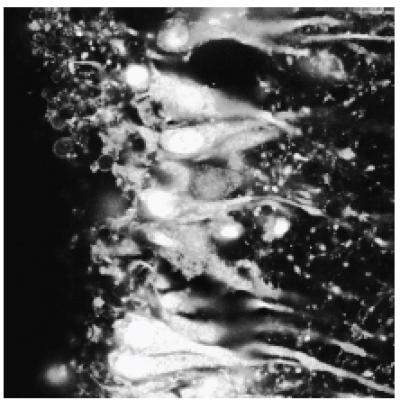

The first tool is a sequence of amino acids that allows the molecules to infiltrate the walls of a cell without damaging it or the surrounding tissue. But rather than targeting a specific cell at this stage, the researchers washed the entire tissue sample from the brain with a solution containing TIVA tags, introducing the molecule to all of the cells.

Because this technique means the molecule is present throughout nerve cells in the brain tissue rather than only in a single cell of interest, the researchers need a way to keep the TIVA tag's mRNA-capturing ability switched off until the time is right. This is accomplished by the tag's second tool, a removable "cage" that covers the molecule's binding site.

The TIVA tag builds on prior work from the Eberwine lab using photoactivation of DNAs and a capture sequence to isolate RNA-binding proteins from live cells, as well as work from the Dmochowski lab, which has been working on various iterations of light-activated oligonucleotides for over a decade. "These molecules are 'caged' in the sense that we're physically blocking their function until we give them the key, which is laser light," Dmochowski says. "Once the cage is off, they're free to do what they want to do: bind to mRNA."

The precision of the blue-activating laser is such that the researchers are able to break open the cages of TIVA tags in a single cell. However, to ensure that these tags have made it into the target cell, they first probe it with a less powerful green laser. This laser interacts with another of the tag's tools: a pair of fluorescent dyes.

These dyes are positioned in a precise way: one is near the poly-U sequence and the other by the poly-A. When the molecule's cage is still locked, they are close enough together that they can transfer energy from the laser between one another. According to Pharmacology's Sul, probing a cell with a green laser and producing a light emission that corresponds to this energy transfer between the dyes is a signal that the tag has made it into the cell intact.

After activating the tags with the more powerful blue laser, the researchers can then probe the cell with the green laser again; the absence of the signal means the dyes are separated and the cage has been removed.